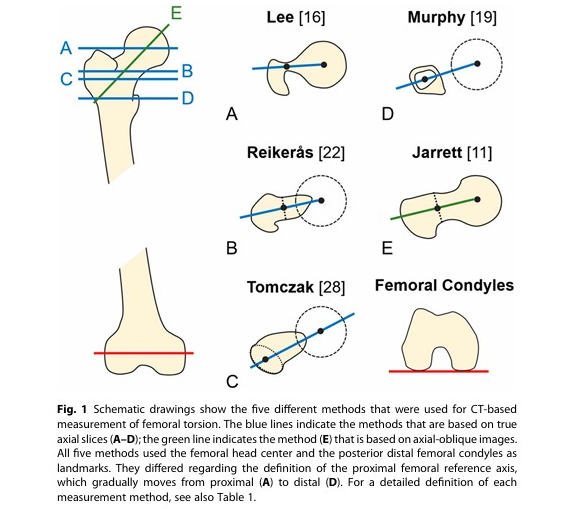

Torsion fémorale

A + B + C (tetefem + colfem + condyles)

A + B + C (tetefem + colfem + condyles)

Torsion tibiale

D + F (plateau + malleol)

TA-GT

C + E (condyles + TTA)

Bascule rotulienne

Grand axe de la rotule (G) et Condyles (C)

Coupes

A

Tête fémorale

B

Col fémoral

Col fémoral

C

Condyles (Arche romaine)

D

Plateaux tibiaux

E

TTA

F

Malléoles tibiales

G

Grand axe de la rotule